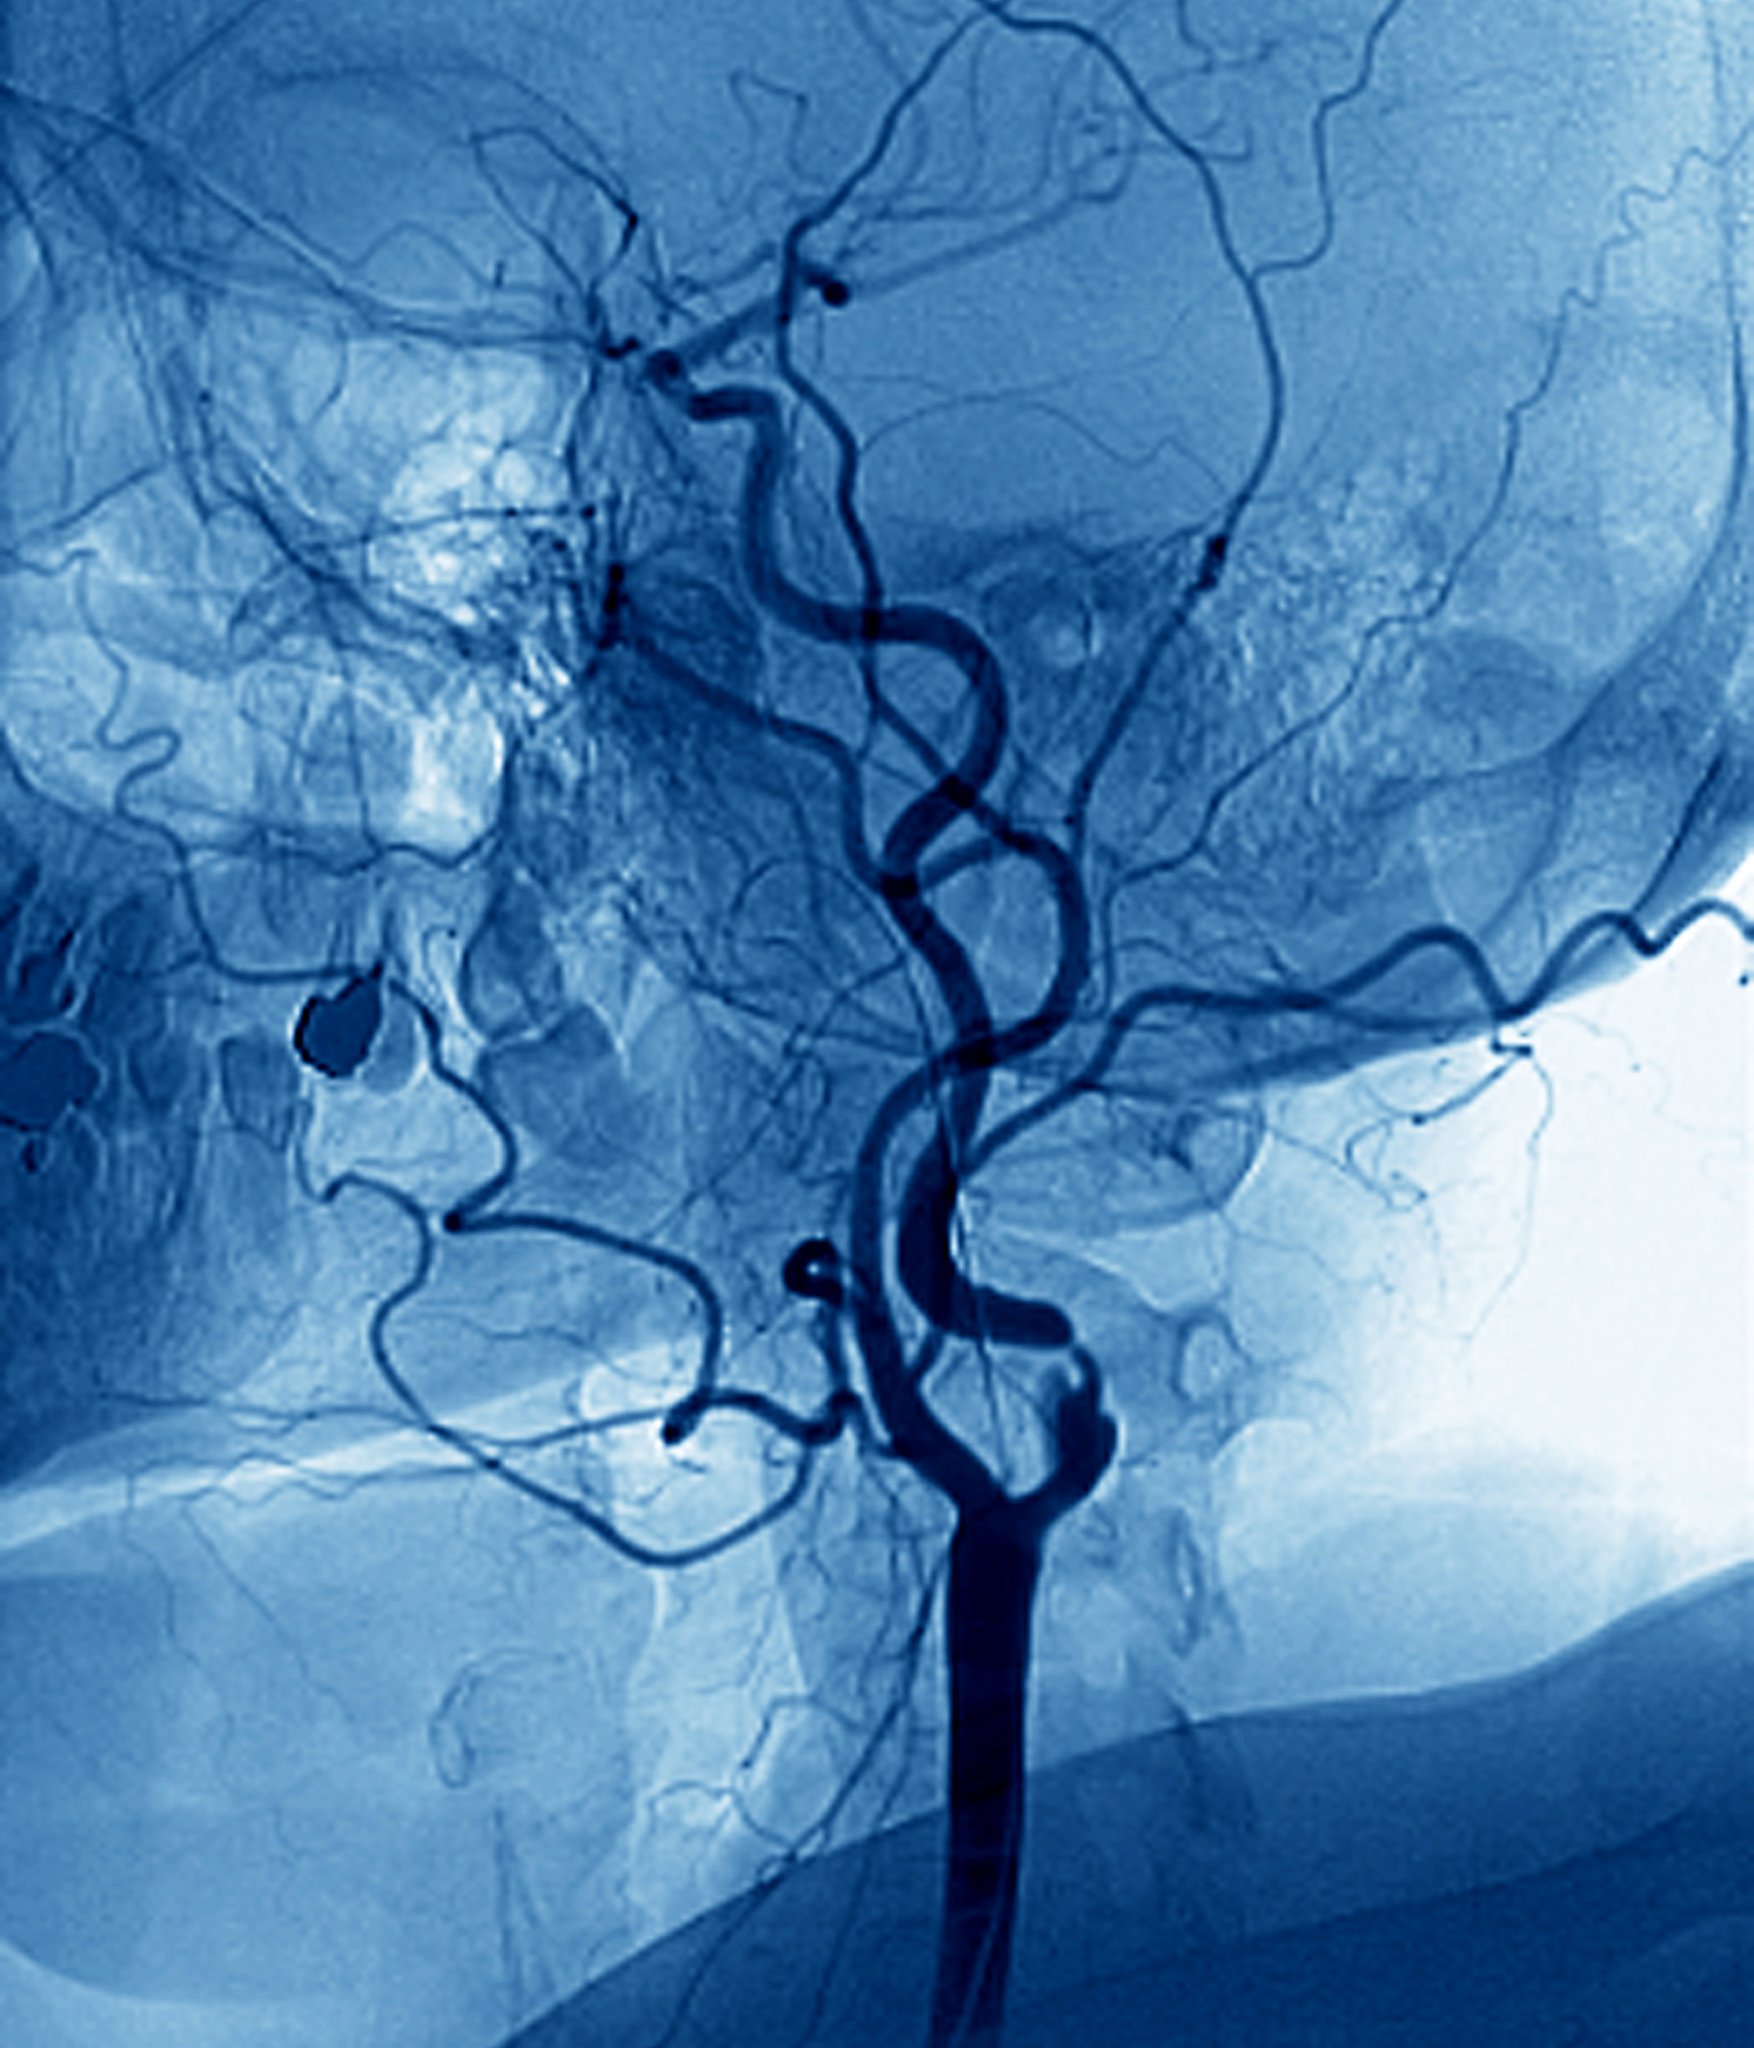

颈动脉斑块破裂:急性中风患者的诊断利器

因此,在急性中风患者中考虑脆弱的颈动脉斑块破裂的潜在可能性非常重要,增强超声成像作为一种有价值的诊断工具。